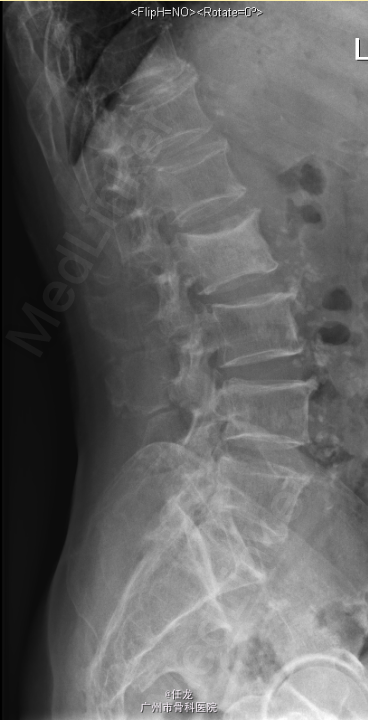

主诉:前列腺癌术后8年,反复腰痛半年,加重2周。 病史:患者8年前曾诊断为前列腺癌,并在外院行手术治疗,并多次放疗,一般坚持门诊复查。半年前出现腰部疼痛,为持续性疼痛,休息后无缓解,无双下肢麻木疼痛。最近两周加重明显,影响睡眠。遂至门诊就诊,门诊MRI考虑:前列腺癌腰椎转,故收入院作进一步诊治,患者一般情况较差。

查体:L2-L4棘突及棘旁轻度叩压痛。四肢感觉、肌力及肌张力正常。双侧坐骨神经出口处无轻压痛。双侧直腿抬高试验(-),双侧股神经牵拉试验(-)。双侧膝反射及踝反射未引出,双侧踝阵挛阴性。双侧Babinski 征及Oppenheim 征(-)。 辅助检查:PSA:73.22ng/ml ↑。腰椎影像学检查如下。

诊断:1. 前列腺癌腰椎转移 2.前列腺癌切除术后 处理:入院后完善相关检查,术前给予对症治疗,科里术前讨论决定:拟行手术:L2-4经皮穿刺活检+术中放疗+椎体成形术。